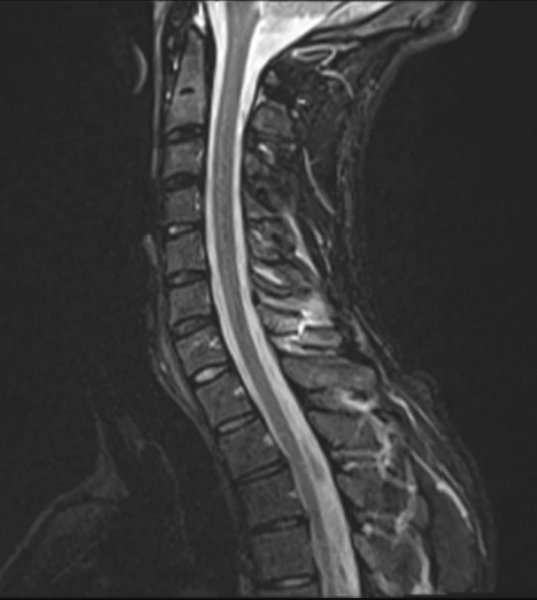

31-летний мужчина обратился в больницу при Лейпцигском университете с жалобой на острую боль и отек в области шейного отдела позвоночника. Он рассказала, что до четырех часов в день играл в VR, часто повторяя одни и те же движения руками, плечами и головой "в соответствии с ритмическими визуальными и музыкальными указаниями".

В результате седьмой шейный позвонков сильно "стерся", а его остистый отросток треснул, не выдержав нагрузок. Как подчеркивают медики, это первый в мире стрессовый перелом из-за виртуальной реальности, обычно от таких травм страдают спортсмены, военнослужащие и шахтеры. Врачи обследовали пациента при помощи магнитно-резонансной томографии и исключили дефект мягких тканей, после чего начали лечение с обезболивающими препаратами. Спустя 6 недель ношения бандажа, немец восстановился без осложнений.